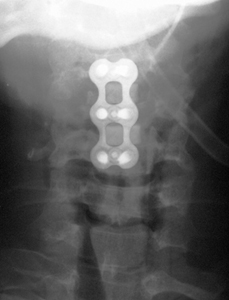

ACDF X-Ray

Anterior Cervical Discectomy & Fusion (ACDF), Instrumented

3. Stabilization of the fusion with a metal plate and screws.

The surgery is performed through a small skin incision in the front of the neck. The esophagus and windpipe are pushed to one side, allowing direct access to the anterior cervical spine. With the aid of a high-powered microscope, the herniated disc and bone spurs can be removed with microsurgical instruments to relieve pressure on the nerves and spinal cord. The fusion is obtained by placing bone graft within the disk space. This bone graft maintains the disc space height and allows bone cells to grow from one vertebra to another. A metal plate and screws are placed over the graft and vertebra to stabilize the spine during the fusion (healing) process. The skin is closed with dissolvable sutures and sterile superglue.